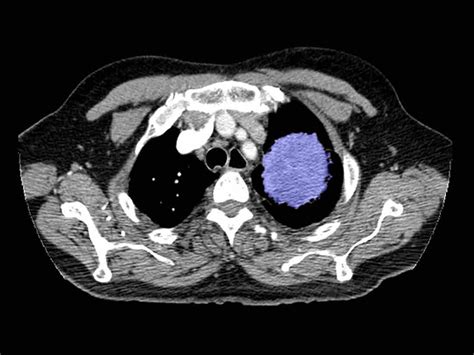

Early Signs Of Lung Cancer On Ct Scan / New type of CT scan may allow doctors to detect lung ... / Most lung cancers do not cause any symptoms until they have spread, but some people with early lung cancer do have symptoms.. Signs and symptoms of lung cancer. Early stage lung cancer often does not have symptoms. Learn more about lung cad systems. The exact cause of lung cancer is still being investigated. Patients with lung cancer are usually asymptomatic during the early stages of the disease.

Ct scans to find lung cancer in smokers. Early signs of lung cancer and why screening is important. Performing a chest radiograph is one of the first investigative steps if a person reports symptoms that may be suggestive of lung cancer. This systemic analysis was conducted to to evaluate the application value of positron emission tomography/computed tomography (pet/ct) in early diagnosis of lung cancer. Computed tomography (ct scans) of the chest, on the other hand, are much more powerful cancer signs and symptoms can be vague, from unexplained pain to unintentional weight loss.

Clinical studies evaluating the application value of pet/ct for patients underwent pet/ct imaging. If you go to your doctor when you first notice symptoms, your cancer might be diagnosed at an earlier stage, when treatment. If you're a current or former smoker. Early warning signs of lung cancer. Performing a chest radiograph is one of the first investigative steps if a person reports symptoms that may be suggestive of lung cancer. It is used to look for early signs of lung cancer. Learn more about lung cad systems. Lung cancer is the most common cause of cancer death worldwide, and there is accumulating higher level evidence that a mortality benefit exists with. Early signs of lung cancer and why screening is important. Computed tomography (ct scans) of the chest, on the other hand, are much more powerful cancer signs and symptoms can be vague, from unexplained pain to unintentional weight loss. Learn about lung cancer early warning signs, symptoms and treatments. However, trials and studies are assessing the effectiveness of lung. Lung cancer screening refers to cancer screening strategies used to identify early lung cancers before they cause symptoms, at a point where they are more likely to be curable.

VCU Medical Center Offers Lung Cancer Screening Program from www.news.vcu.edu Computed tomography (ct scans) of the chest, on the other hand, are much more powerful cancer signs and symptoms can be vague, from unexplained pain to unintentional weight loss. Ct screening for lung cancer has only been studied in people at high risk of lung cancer — those with a long smoking history and who are 55 and older. Fortunately, early detection of the cancer can drastically improve survival rates. Unless this is correlated with other findings, such as a. Read the american cancer society's lung cancer screening guidelines for individuals who are at high risk of lung cancer due to cigarette smoking. When lung cancer does cause signs in its early stages, they may vary from person to person but commonly include: This may reveal an obvious mass, the widening of. This systemic analysis was conducted to to evaluate the application value of positron emission tomography/computed tomography (pet/ct) in early diagnosis of lung cancer.

A new cough that is. Clinical studies evaluating the application value of pet/ct for patients underwent pet/ct imaging. Preventive services task force (uspstf) that is why lung cancer screening is recommended only for adults who are at high risk for developing the disease because of their smoking history and age, and who do. If you're a current or former smoker. Early stage lung cancer often does not have symptoms. Lung cancer early detection | lung cancer screening. Most lung cancers don't cause symptoms until the disease has advanced, in part because the lungs have few nerve endings. Early warning signs of lung cancer. Most lung cancers do not cause any symptoms until they have spread, but some people with early lung cancer do have symptoms. Or you may notice some common signs computed tomography (ct) scans can detect smaller tumors. Learn more about lung cad systems. Evolution of a neural network prediction. Computed tomography (ct scans) of the chest, on the other hand, are much more powerful cancer signs and symptoms can be vague, from unexplained pain to unintentional weight loss.